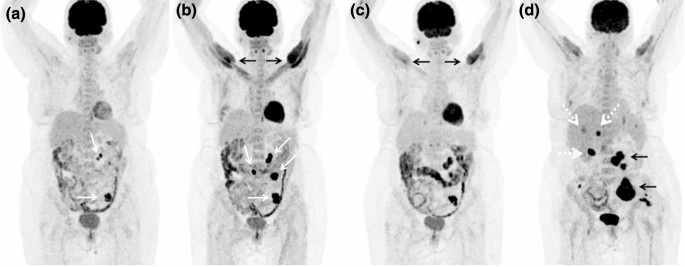

The beauty of the Axumin PET scan is that it offers the possibility to detect small metastatic lesions with PSA levels in the range of 1 to 10 in the lymph nodes. What Are Side Effects of Axumin. So he did Axumin PET and MRI but two scans show different results.

This means that a negative Axumin PETCT scan does not rule out that you have recurrent prostate cancer and a positive Axumin PETCT scan does not confirm that you have recurrent. This means that a negative Axumin PETCT scan does not rule out that you have recurrent prostate cancer and a positive Axumin PETCT scan does not confirm that you have recurrent. Historically simple bone scans and CAT scans required PSA levels in the 10 to 50.

Axumin fluciclovine F 18 injection is a diagnostic imaging agent sometimes called a radiotracer. Studies show the Axumin scan incrementally more sensitive than the C11 scans especially at earlier stages of recurrence or persistence in my case. Learn more about imaging with PYLARIFY now.

Axumin is indicated for Positron Emission Tomography Computed Tomography PETCT imaging in men with suspected prostate cancer recurrence based on elevated blood. For years we have been able to detect. I was diagnosed with gleason 6 prostate cancer 5 years ago.

Cancers Free Full Text 18f Fluciclovine Pet Ct Improves The Clinical Management Of Early Recurrence Prostate Cancer Patients Html

Biomedicines Free Full Text Detection Rate And Clinical Impact Of Pet Ct With 18f Facbc In Patients With Biochemical Recurrence Of Prostate Cancer A Retrospective Bicentric Study Html